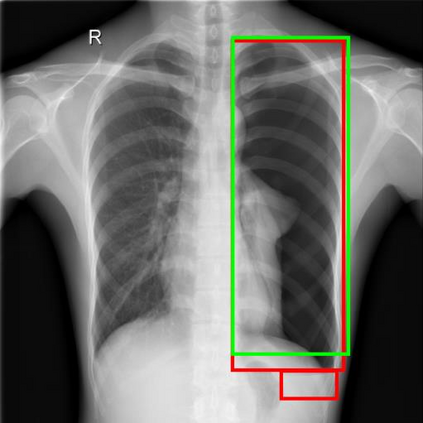

Chest X-ray (CXR) is the most typical diagnostic X-ray examination for screening various thoracic diseases. Automatically localizing lesions from CXR is promising for alleviating radiologists' reading burden. However, CXR datasets are often with massive image-level annotations and scarce lesion-level annotations, and more often, without annotations. Thus far, unifying different supervision granularities to develop thoracic disease detection algorithms has not been comprehensively addressed. In this paper, we present OXnet, the first deep omni-supervised thoracic disease detection network to our best knowledge that uses as much available supervision as possible for CXR diagnosis. We first introduce supervised learning via a one-stage detection model. Then, we inject a global classification head to the detection model and propose dual attention alignment to guide the global gradient to the local detection branch, which enables learning lesion detection from image-level annotations. We also impose intra-class compactness and inter-class separability with global prototype alignment to further enhance the global information learning. Moreover, we leverage a soft focal loss to distill the soft pseudo-labels of unlabeled data generated by a teacher model. Extensive experiments on a large-scale chest X-ray dataset show the proposed OXnet outperforms competitive methods with significant margins. Further, we investigate omni-supervision under various annotation granularities and corroborate OXnet is a promising choice to mitigate the plight of annotation shortage for medical image diagnosis.